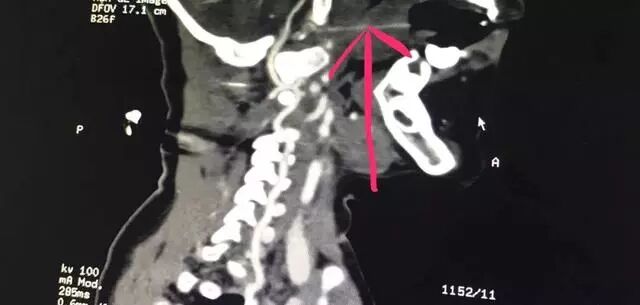

接診的醫(yī)護(hù)人員迅速為患兒安排了病床并實施了相關(guān)檢查。CTA檢查、顱腦CT、三維重建等一系列檢查顯示,長達(dá)13厘米的竹簽經(jīng)過小姑娘的口腔,直指環(huán)樞椎關(guān)節(jié)間隙,緊緊抵住人體最致命部位之一的椎動脈。

患兒的影像資料印證了醫(yī)務(wù)部孔心涓主任的擔(dān)心:

竹簽刺入的部位極其特殊而兇險,如果竹簽有一丁點挪動,可能會導(dǎo)致椎動脈被刺破,患兒就會有生命危險。